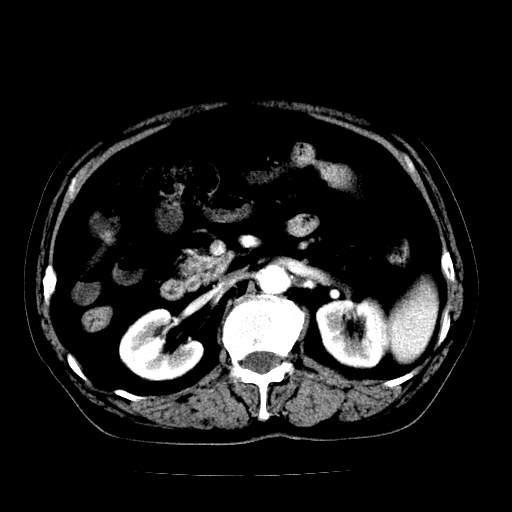

男,71岁,皮肤黄染四天。

考虑胆总管癌并肝内外胆管扩张。

胰腺上端胆总管内见软组织影,强化不明显,结合临床,还是考虑低位梗阻性黄疸,胆总管癌可能性大